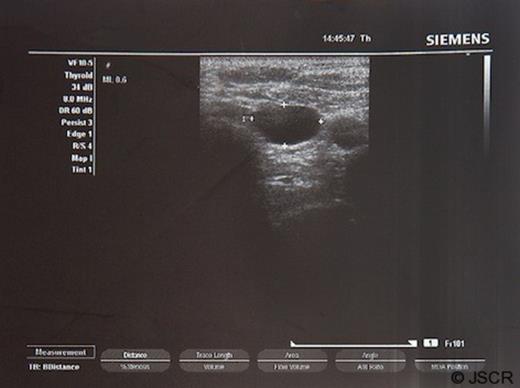

A 56-year-old woman presented with a left-sided cervical lump with three months history. She had been received the diagnosis of goitre at other institute. No dyspnea, swallowing disturbance or voice changes were recorded. At the physical examination, a soft, roundish, painless mass was palpable on the left side of thyroid. Ultrasound of the neck revealed a cystic mass in the left lower pole of the thyroid 2×1 cm in size and the radiologist suspected the diagnosis of thyroid nodule or parathyroid mass (Figure 1).

Ultrasonographic view of the neck revealed a cystic mass in the left pole of the thyroid